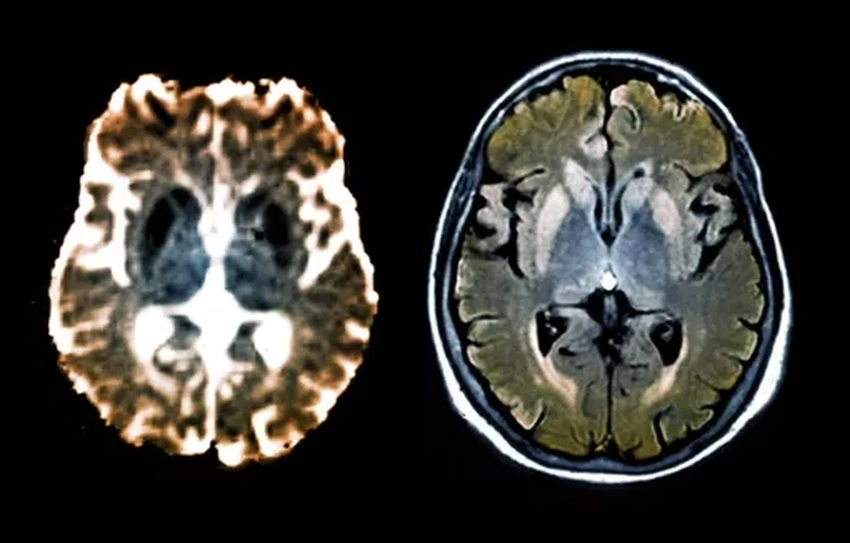

Многие нейродегенеративные болезни — Альцгеймера, Паркинсона — это, по сути, трагедия на молекулярном уровне. Гены сбиваются с ритма и начинают штамповать белки с фатальными ошибками. Эти белки-уродцы засоряют и убивают нейроны. Но что, если просто остановить этот бракованный конвейер, не трогая сам чертёж — ДНК? Природа знает этот трюк и использует его постоянно — через процесс метилирования. Исследователи просто направили этот природный механизм точно в цель: заставили гены, производящие смертельные прионы, замолчать. Просто и гениально.

А теперь давайте познакомимся с героем дня. Пенсильванские учёные представили молекулярный инструмент под скромным именем CHARM. В отличие от своего знаменитого «коллеги» CRISPR/Cas9, который работает как молекулярные ножницы, вырезая куски ДНК, CHARM — это больше дипломат, чем солдат. Он не режет, а вешает на нужные гены химические «ярлыки» — метильные группы. Эти метки — сигнал «тише, пожалуйста», который снижает активность гена. В эксперименте CHARM успешно угомонил ген, производящий прионные белки в нейронах мозга мышей.

Когда CHARM доставили в мозг мышей, результат превзошёл ожидания: производство рокового белка PrP упало более чем на 80% по всему мозгу. Это намного выше минимального порога, необходимого для терапевтического эффекта! А после выполнения миссии CHARM, словно агент-невидимка, самоуничтожается, не оставляя следов в клетке. Идеальный инструмент.